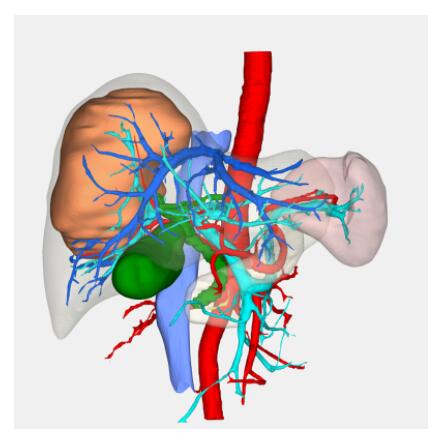

Segmentation

Segmentation of tissue (e.g., isolating the brain, differentiating gray and white matter) is performed using region-growing methods, filter operations as well as the application of 3D templates. Using the mouse it is very easy to explore a 3D volume with superimposed pseudocolor-coded statistical maps in a four-window representation showing a sagittal, coronal, transversal and oblique section. Based on a (segmented) 3D data set a three-dimensional reconstruction of the subjects' head and brain can be calculated and displayed from any specified viewpoint using volume or surface rendering.

Volume Rendering

Volume rendering is performed with a very fast ray casting algorithm; lightning calculations are based on Phong-shading. Surface rendering of reconstructed surfaces is performed using OpenGL. Using texture mapping, a reconstructed surface (e.g., head or brain) may be sliced in real time, showing both surface and volume data at the same time. Initial polygon meshes serve as the basis for surface finding, cortex inflation and cortex flattening computations.